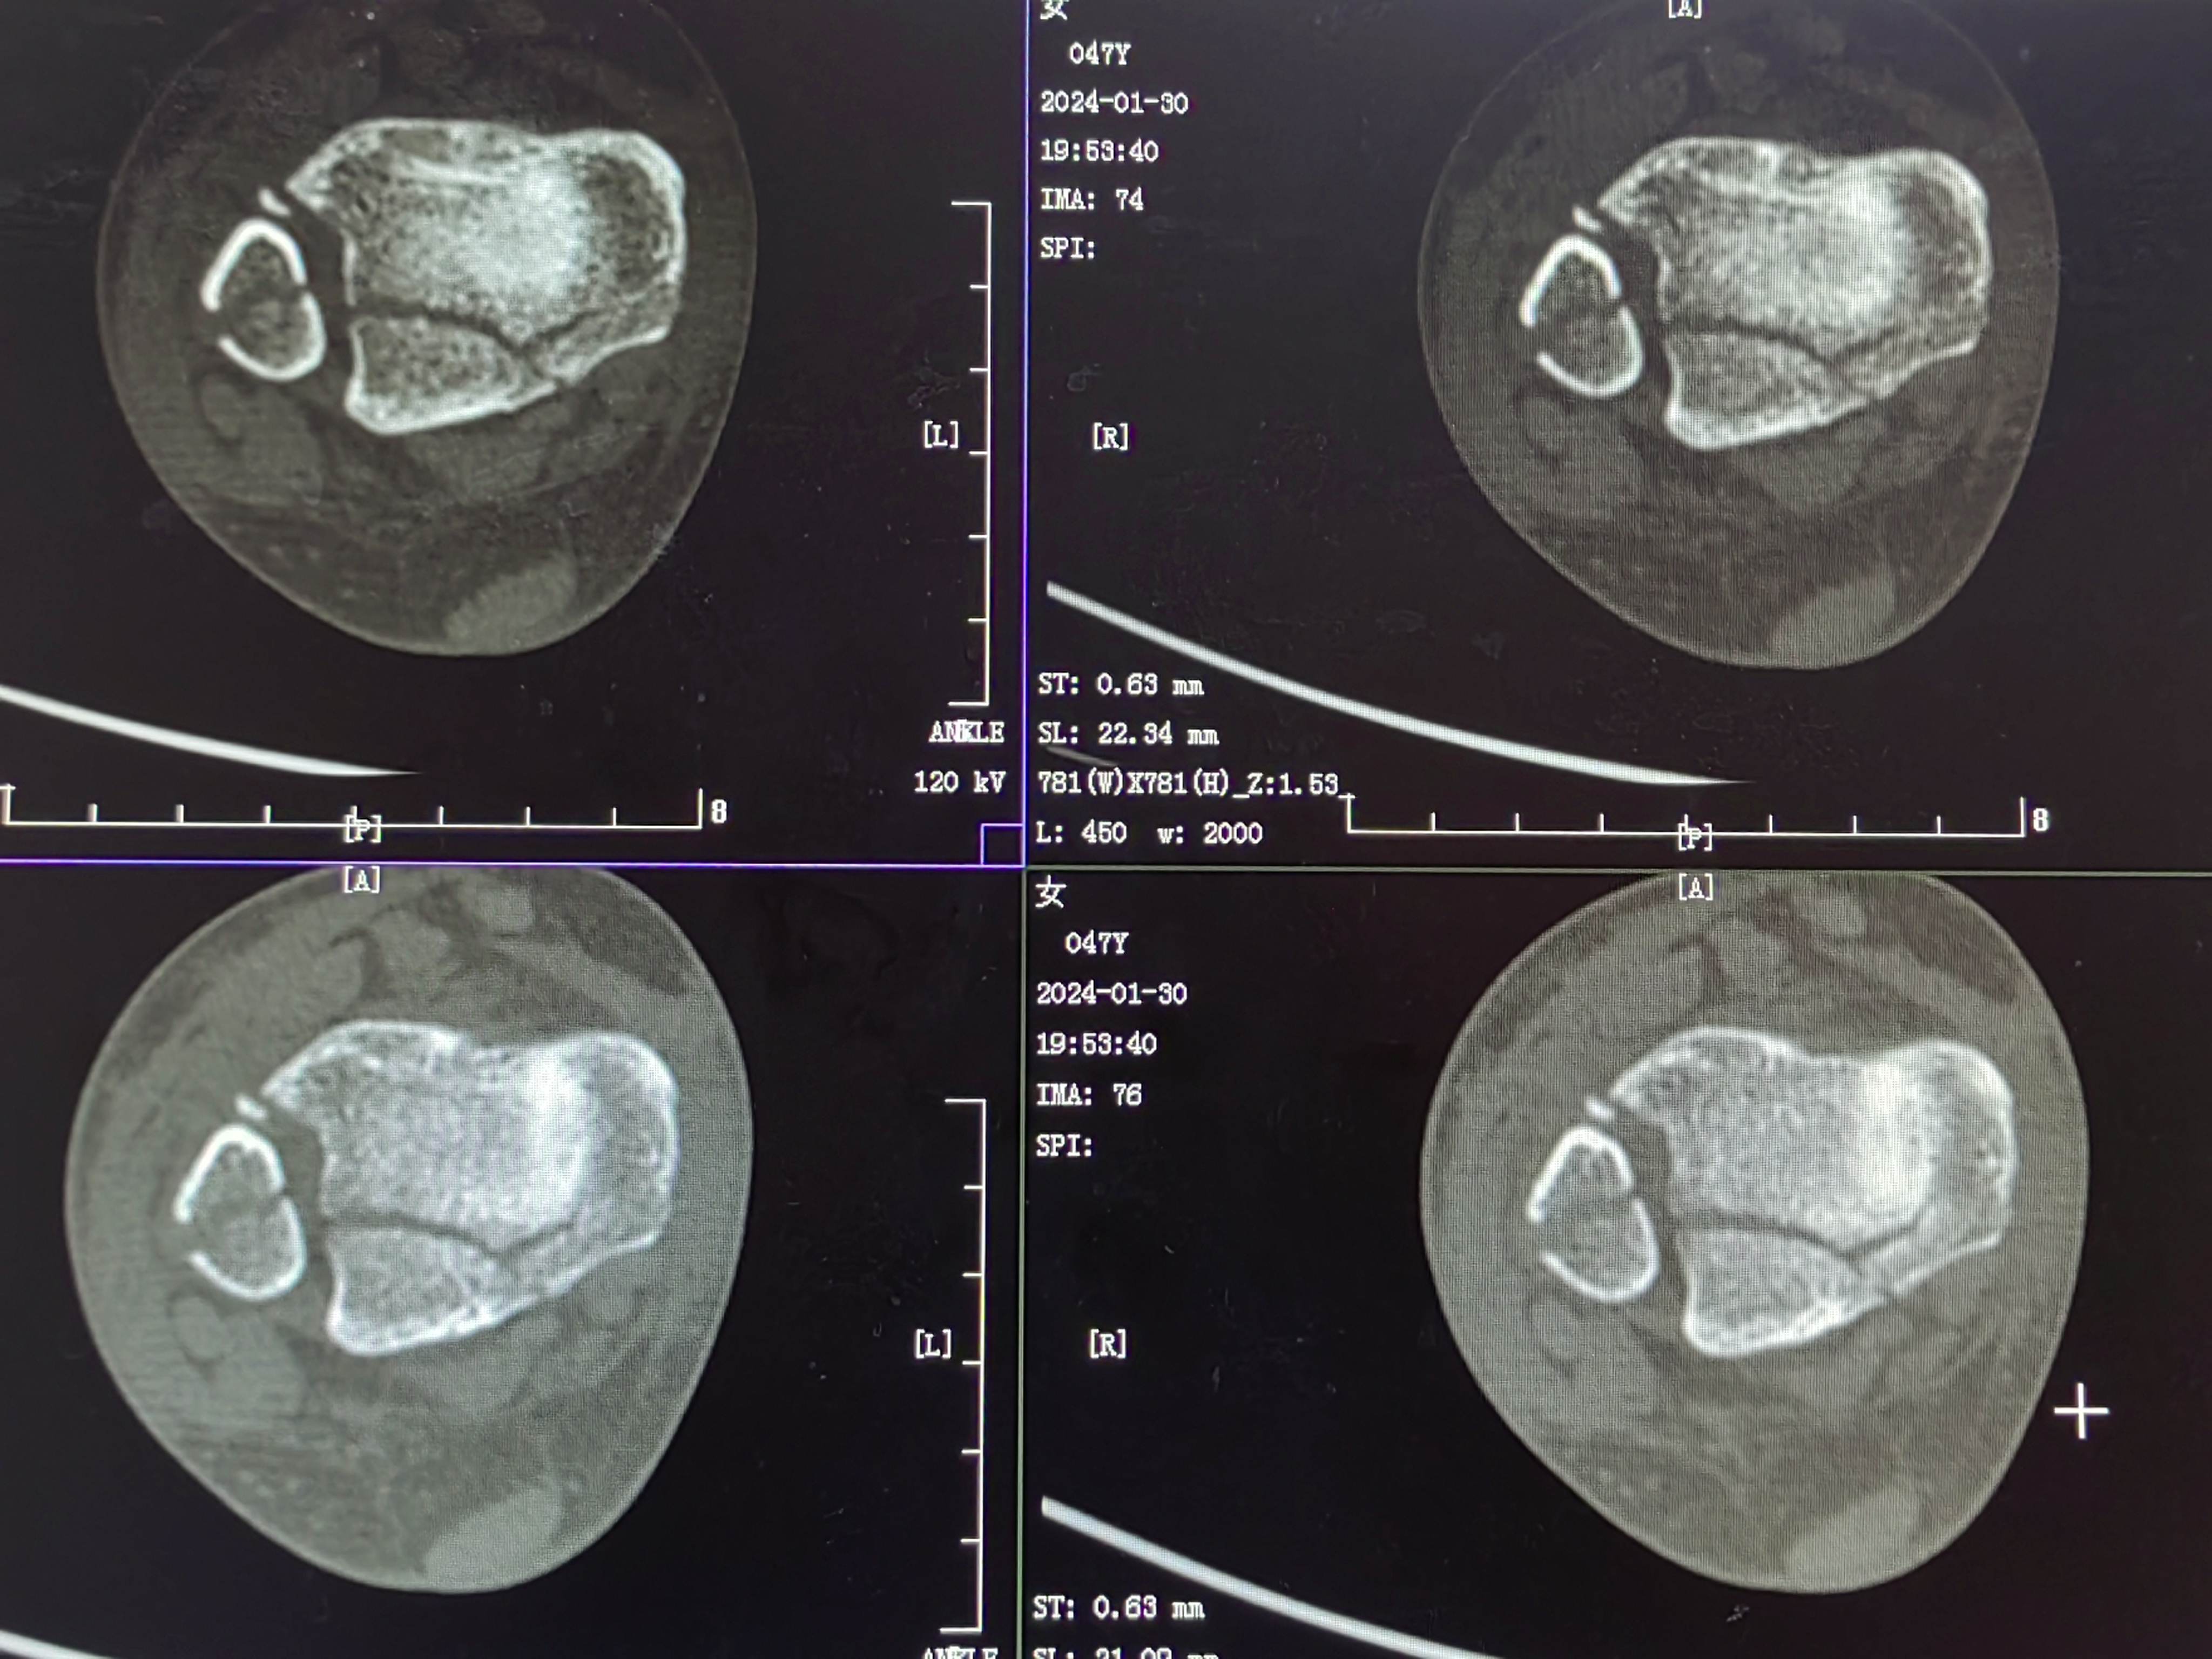

首诊三维CT